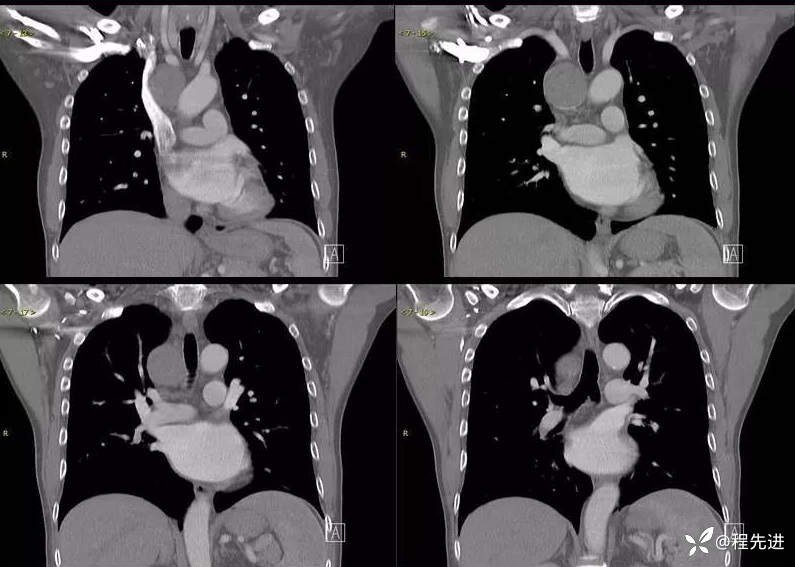

增强静脉期冠状位